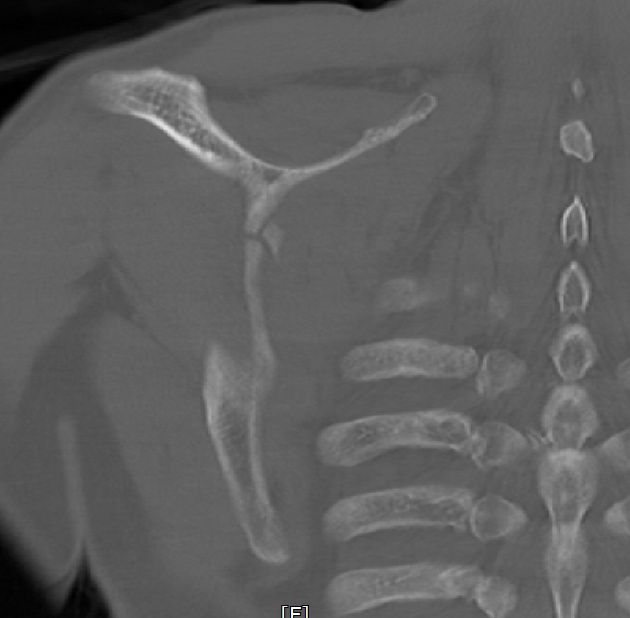

2022.06.07 CT SCAN

- M/50대

- fall down

- X-Ray 검사 상 견갑골 골절의심 됨

- Axial Scan 후 MPR로 Axial, Coronal, Sagittal image Recon 함

- Rib CT 포함하여 검사함.

mildly displaced fracture of body of scapula.